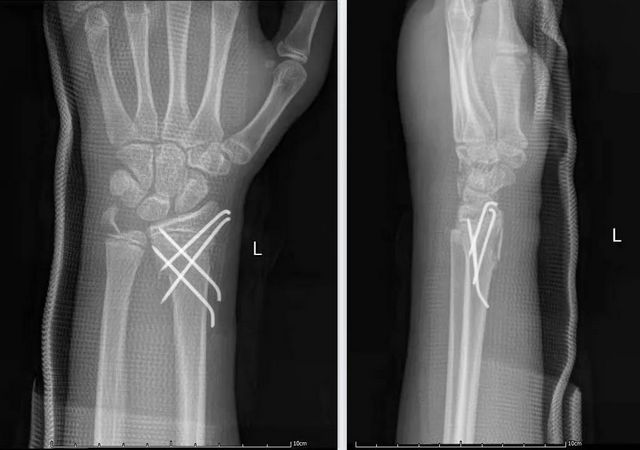

根据患儿情况,陈孝均主任与贺智榆医生决定采取保守石膏夹板固定、微创克氏针手术治疗等方式,经过治疗,三个孩子都顺利出院。